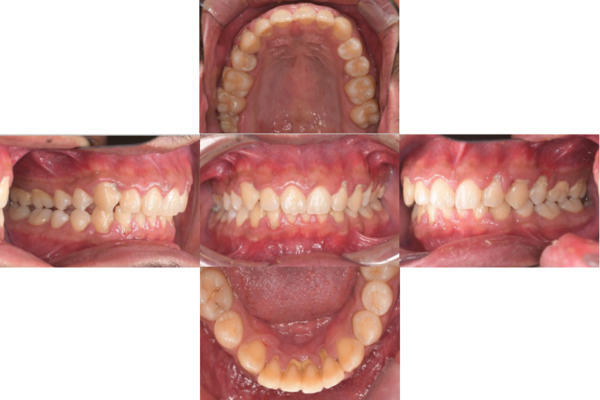

症例5

before

症例

after

歯周病検査(治療前)

歯周病検査(治療後)

レントゲン写真

基本情報

年齢・性別 32歳・男性

主訴 主訴:歯ぐきから出血する

治療部位:全顎

治療内容 「全顎」

歯周基本治療(歯周精密検査、スケーリング、OHI、SRP)

治療期間 約3ヶ月

治療費 歯周基本検査:約600円(保険診療3割負担)

スケーリング、OHI:約2,000円(保険診療3割負担)×2回

SRP、OHI:約1,500円(保険診療3割負担)×4回

歯周精密検査:約1,200円(保険診療3割負担)×2回

合計金額13,000円

(2025年2月現在)

リスク・副作用 歯石を取った後に、歯がしみることがあります。

治療方針 ①検査

レントゲン、口腔内写真を撮影して、歯や歯周組織の状態を確認します。

また、歯周病の検査で歯周ポケットの深さや出血の有無を確認します。

②スケーリング、OHI(口腔衛生指導)

スケーリングをして歯の表面の歯石を除去します。

また、正しい歯磨きの仕方や、フロスの通し方を一緒に確認します。

③歯周精密検査

前回歯石除去と歯磨き指導を行なった結果、歯ぐきの状態がどれぐらい改善したか検査します。

④SRP

歯ぐきの内側についてる歯石を除去します。

⑤歯周精密検査

SRP後、歯周病が改善されたか、検査します。

歯周ポケットが4ミリ以上の部位は、再度SRPを行います。

今回は歯周病の状態が安定したため、3ヶ月おきの定期検診で歯周病の再発や進行を防ぎます。

特記事項 歯周精密検査について:

・歯周ポケットが4ミリ以上ある場合は歯周病で、3ミリ以下は健康な歯ぐきです。

・出血の有無で炎症があるか確認します。

・磨き残しがある部分を確認して記録します。

担当者所見 初診時は、写真を見て分かるように、歯ぐきが赤く腫れていました。

また、歯周病の検査では、全体的に歯と歯の間の部分の歯周ポケットが4ミリあり、全体の約81%から出血が認められました。

出血量も多く、歯ぐきに触れた瞬間に出血しました。

レントゲンで骨のレベルがしっかりとあることが確認できました。

そのため、ご自身で正しい歯磨きを継続することで改善すると考えました。

歯周基本治療を経て、再度検査した結果、歯周ポケットはほぼ3ミリ以下に改善しました。左下7番の残存した歯周ポケットは、隣の親知らずを抜いたため経過観察します。

出血率は約4%まで改善し、出血量も点状で少なくなりました。

今後は右上2番、右下3番の歯ぐきの発赤の改善と、出血率0%を目指して、定期検診でメンテナンスしていきます。